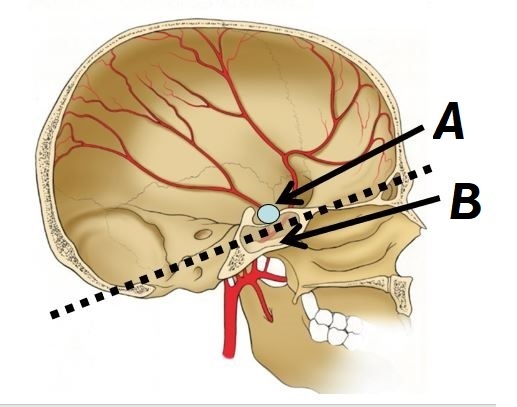

Name structure A and region B

A - Infundibulum

B - Diaphragm sellae